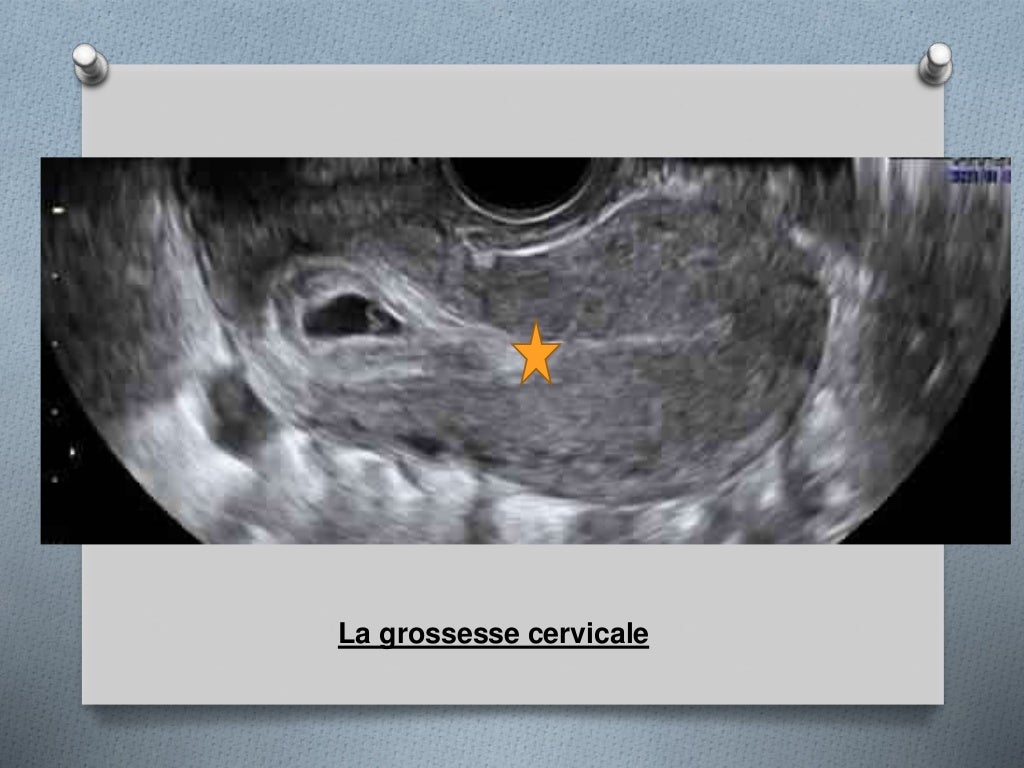

Grossesse sur cicatrice de césarienne rapport de cas et revue de la littérature Gunaikeia. Après la césarienne, la jeune mère se retrouve avec une cicatrice d'une dizaine de centimètres. Bien que courant, l'accouchement par césarienne nécessite une attention particulière pendant la période de récupération